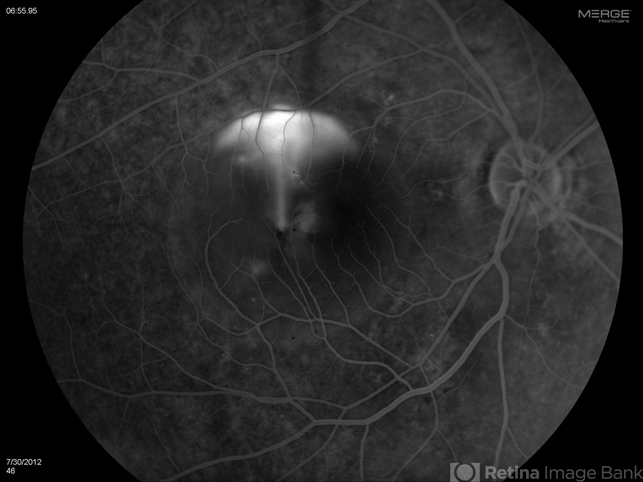

- CSCR mushroom cloud

- CSCR subfoveal leak

- Diana Bodnar, COT

Topcon 50X with OIS capture station - Description

- Late transit FA of a large active subfoveal CSCR leak. Focus is on peri-foveal vessels to give sense of height of large serous RD of macula. This patient presented with a BCVA of 20/200 and fluorescein and historic evidence of prior episodes of leakage. After discussion of known treatment options including observation, he was initially treated with rifampin and had partial resolution to 20/70 BCVA but this was short-lived with reaccumulation of the large serous detachment within 3 months. He then received sub-threshold micro-pulse laser photocoagulation with an 810 nm diode laser which resulted 1 month later in complete drying of the serous detachment and BCVA of 20/25.